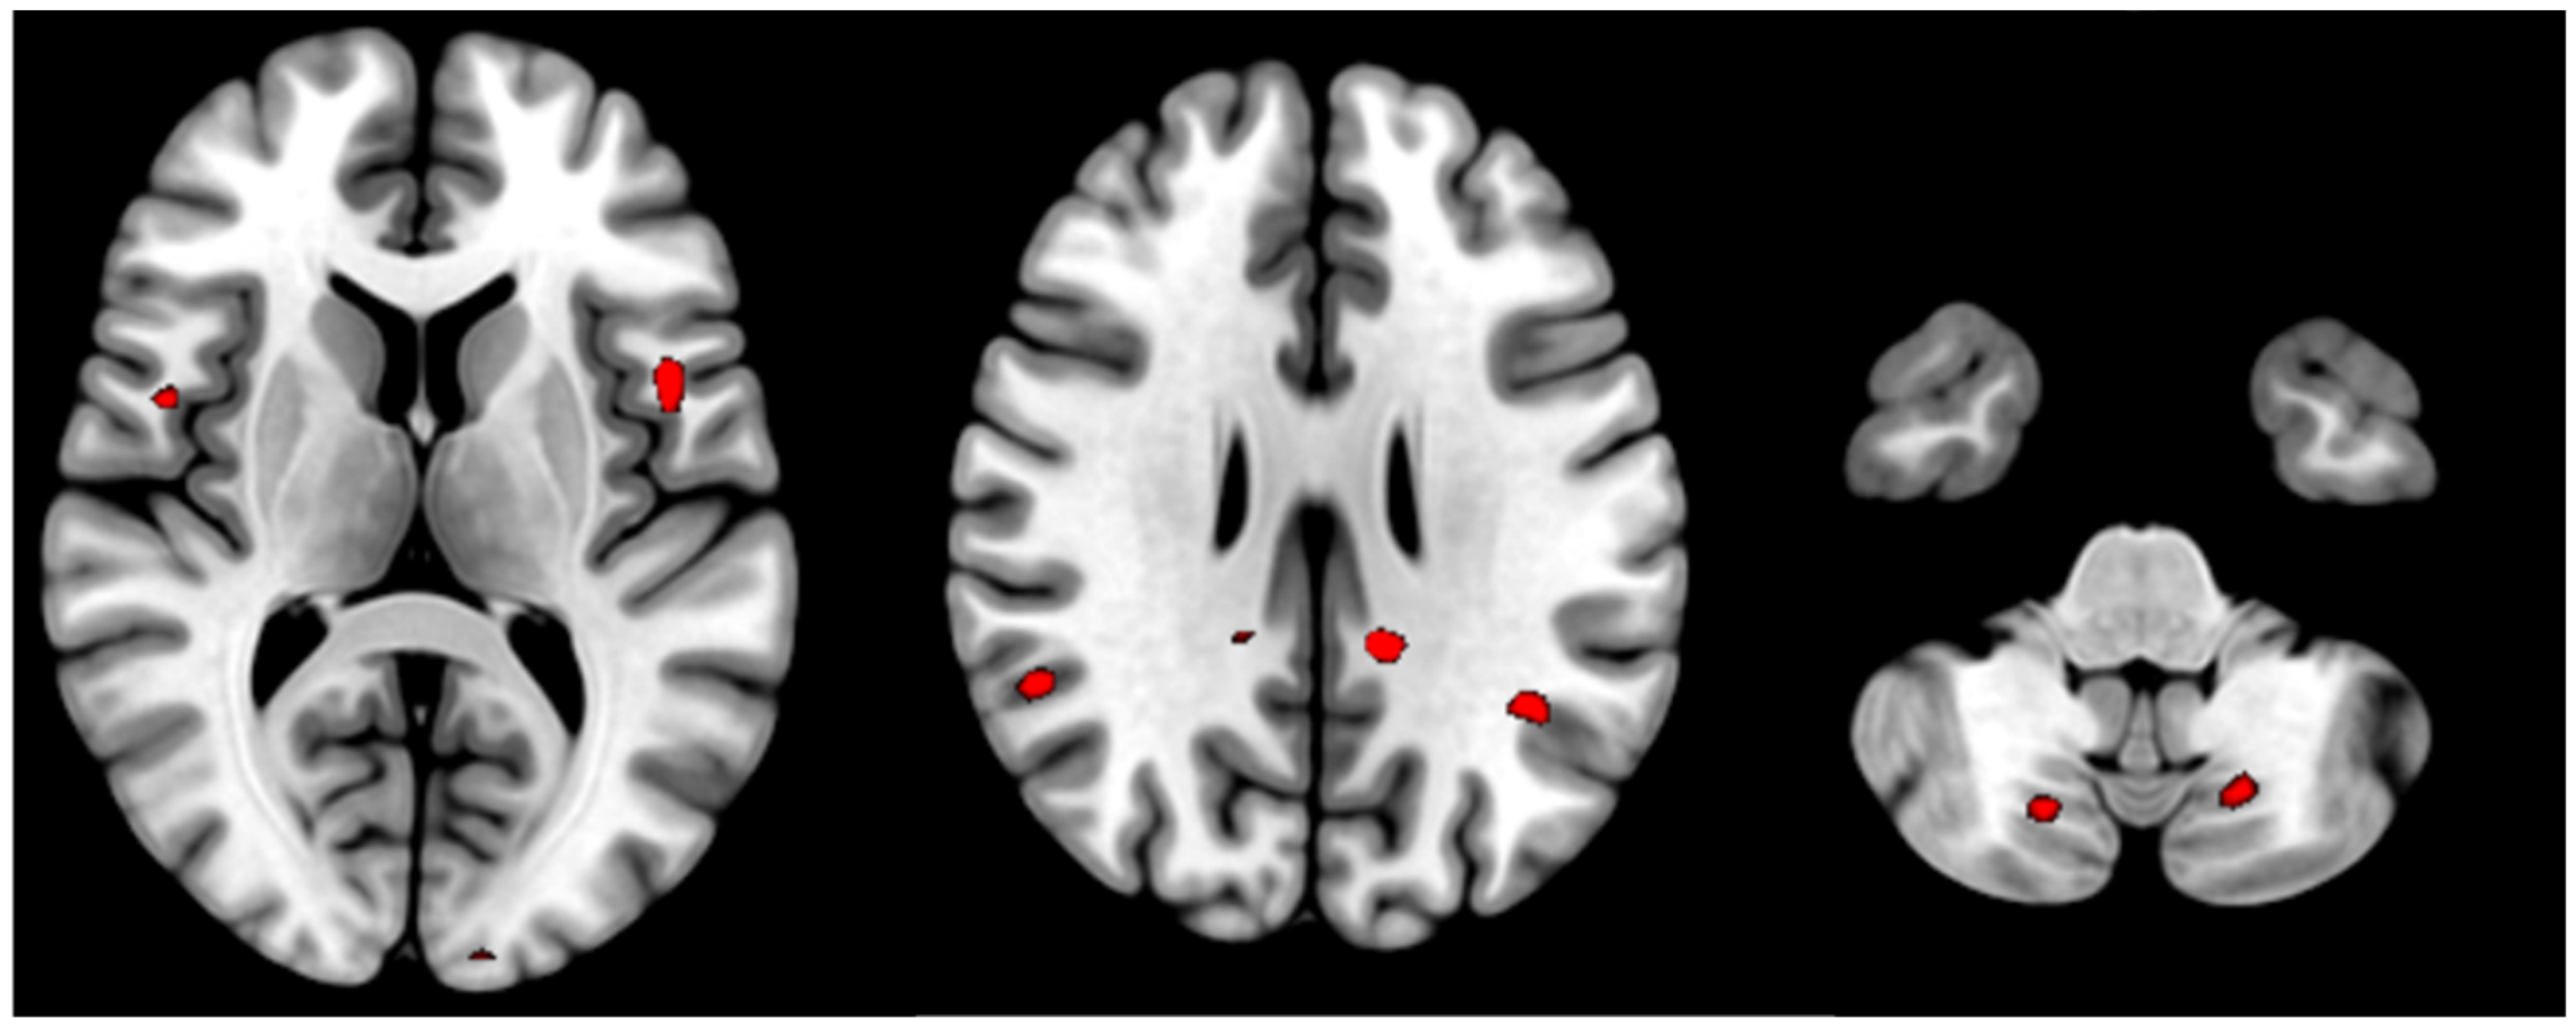

| T | Puncorr | Number of Voxels | Peak MNI Coordinate | |

|---|---|---|---|---|

| Posterior cingulate cortex (L) | 4.06 | <0.000 | 14 | −12 −42 28 |

| Posterior cingulate cortex (R) | 3.32 | 0.001 | 2 | 6 −44 50 |

| Supramarginal gyrus (L) | 3.37 | <0.000 | 23 | −38 −54 30 |

| Supramarginal gyrus (R) | 3.49 | <0.000 | 22 | 52 −50 22 |

| Opercular part of Precentral gyrus (L) | 3.77 | <0.000 | 12 | −46 8 8 |

| Opercular part of Precentral gyrus (R) | 3.47 | 0.001 | 11 | 48 4 10 |

| Cerebellum Posterior Lobe (8) (L) | 3.33 | 0.001 | 67 | −18 −68 −42 |

| Cerebellum Posterior Lobe (8) (R) | 3.25 | 0.001 | 34 | 18 −70 44 |